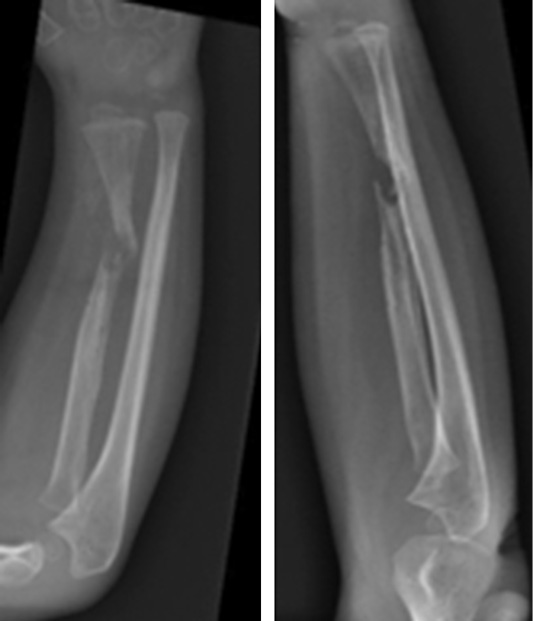

Клинически, как и по данным рентгенологического исследования, у пациента наблюдалось местное улучшение. Спустя 6 мес. после последней трансплантации спица Киршнера была удалена. При контрольном осмотре через 28 мес. у пациента зарегистрированы полная консолидация начального участка несращения, отсутствие нейроваскулярной недостаточности и суставной недостаточности. Больного можно считать выздоровевшим (рис. 7, 8).

Рис. 7. Рентгенограмма после удаления спицы Киршнера через 28 мес. после травмы

Рис. 8. Клиническая картина через 28 мес. после травмы